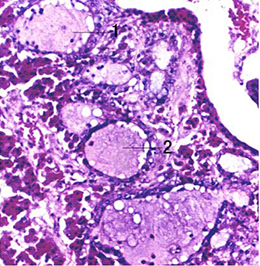

照片名称:27腺垂体

(图) ~14 脑垂体(光镜结构)

脑垂体远侧部和中间部模式